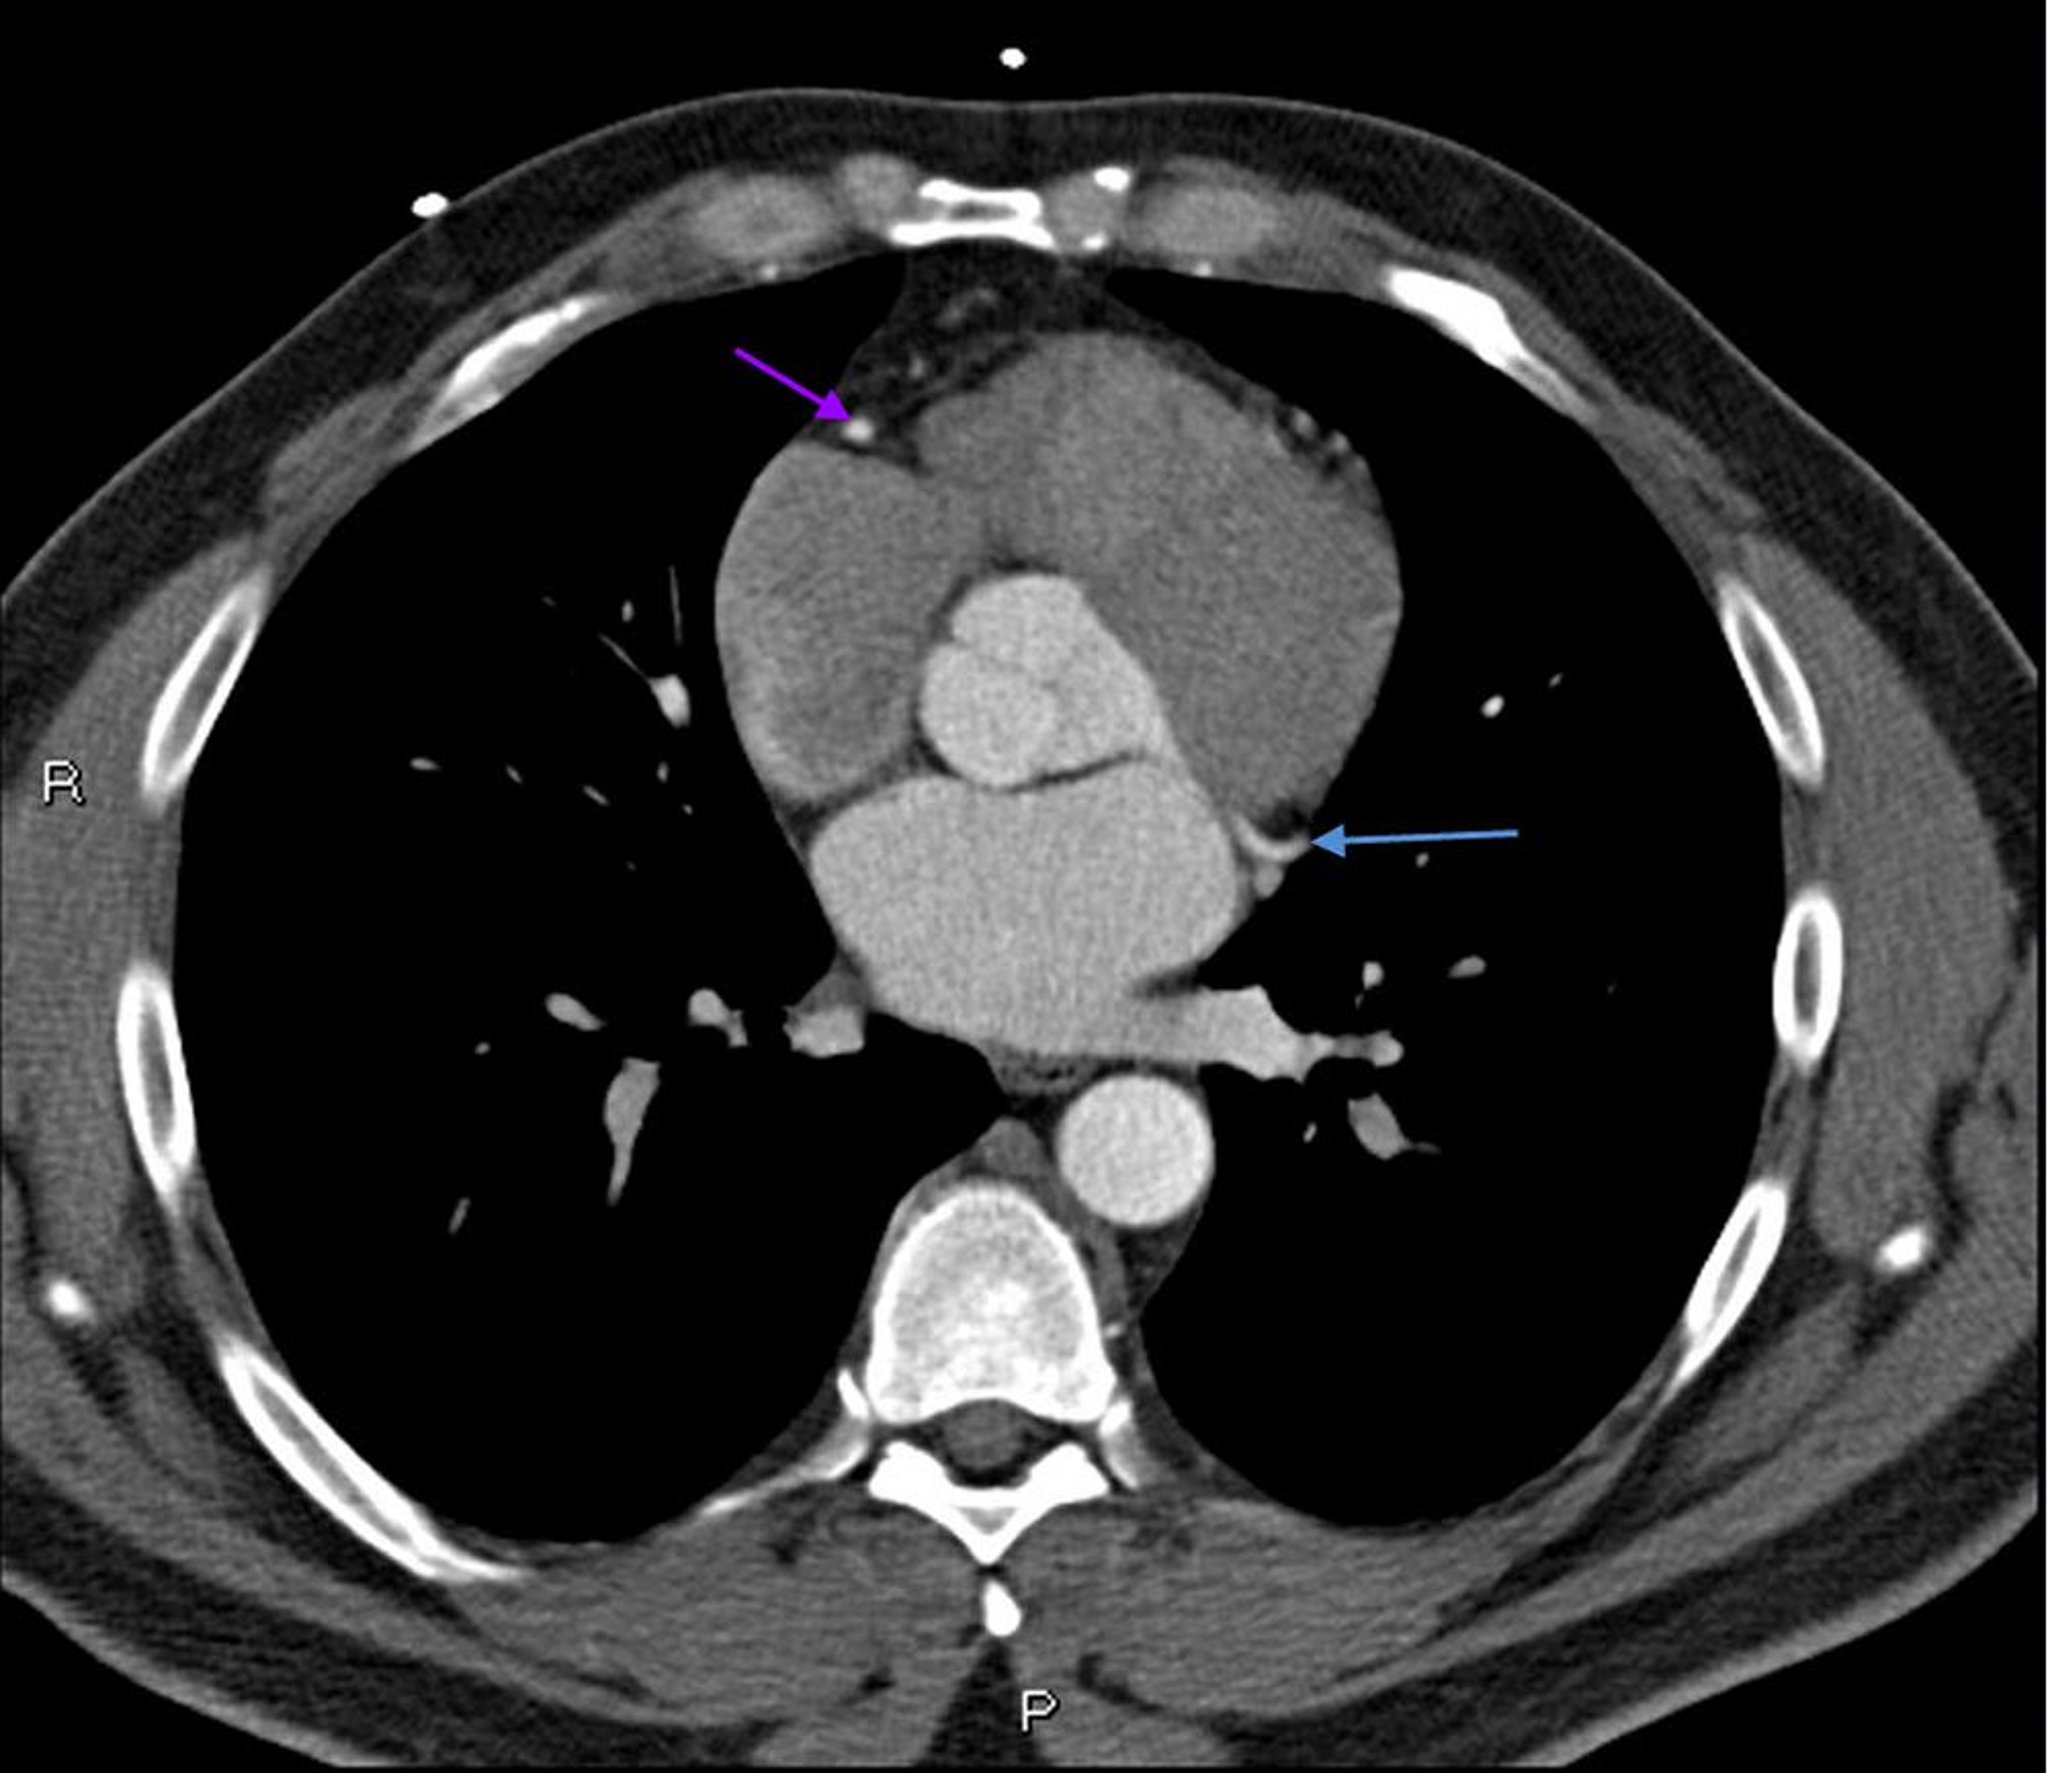

Contrast CT Showing Normal Coronary Arteries – Slide 6

This contrast CT shows normal coronary arteries. The left main is indicated by the red arrow. The left anterior descending and left circumflex arteries are indicated by the green and blue arrows respectively and the right coronary artery is indicated by the purple arrow.